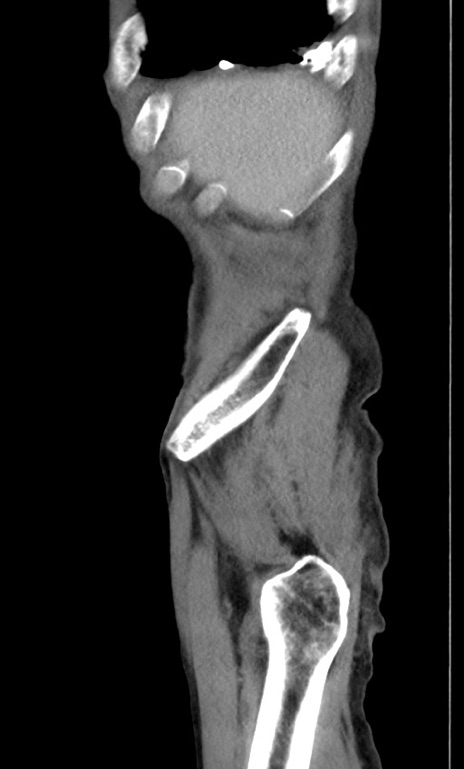

症例3(矢状断像)

【症例】 70歳代男性

【主訴】右鼠径部腫瘤、疼痛

【現病歴】本日朝より上記主訴あり、受診。

【既往歴】膀胱癌にて膀胱全摘、両側尿管皮膚瘻

【データ】WBC 5600、CRP 0.56